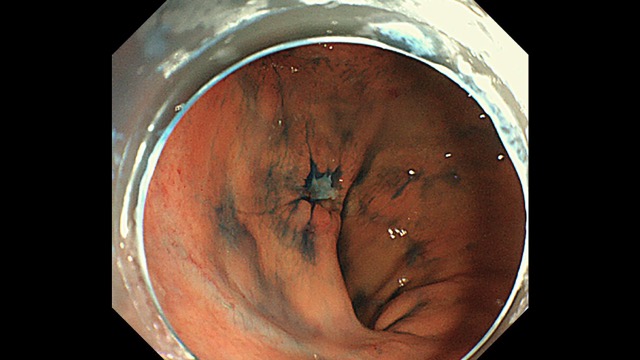

Gastrointestinal Mapping ~Stomach~ 2025.8.27